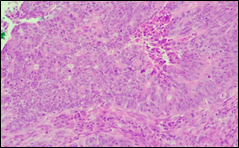

The present study concluded that, out of the total 77 patients with colorectal neoplasia, 17 (22.1%) had a high degree of differentiation (G1), 51 (66.2%) had a moderate degree of differentiation (G2), and 9 (11.7%) had a low degree of differentiation (G3). Figure 3 illustrates the different morphopathological forms of colorectal neoplasia observed in the patients included in the study.

A | B |

C | |

Fig. 3 Morphopathological forms of colorectal tumors (degree of differentiation) A – conventional highly differentiated colonic adenocarcinoma (G1) (HE stain, ×200) B – moderately differentiated (G2) conventional colonic adenocarcinoma (HE stain, ×200) C – conventional poorly differentiated colonic adenocarcinoma (G3) (HE stain, ×200) | |

For patients with colorectal neoplasm, investigating the correlation between the macroscopic aspect of the tumor formation visualized endoscopically and the degree of differentiation described histologically, it was found that there is no statistically significant relationship (p > 0.05), which is above the threshold accepted for demonstrating a significant statistical correlation. It is known that most colorectal adenocarcinomas develop at the site of precursor lesions, such as adenomas and dysplasia. Residual adenoma is a phenomenon commonly found in colorectal adenocarcinomas. Typical adenomas are subclassified into tubular, tubulovillous, and villous types based on their architectural and histological features. Tubular adenomas consist of dysplastic glands that resemble cryptic intestinal glands and contain less than 25% villous component. Villous adenomas are composed of more than 75% villous components, which appear as fibrovascular rods covered by dysplastic epithelium. Tubulovillous adenomas represent intermediate lesions with a villous component ranging from 25% to 75%.